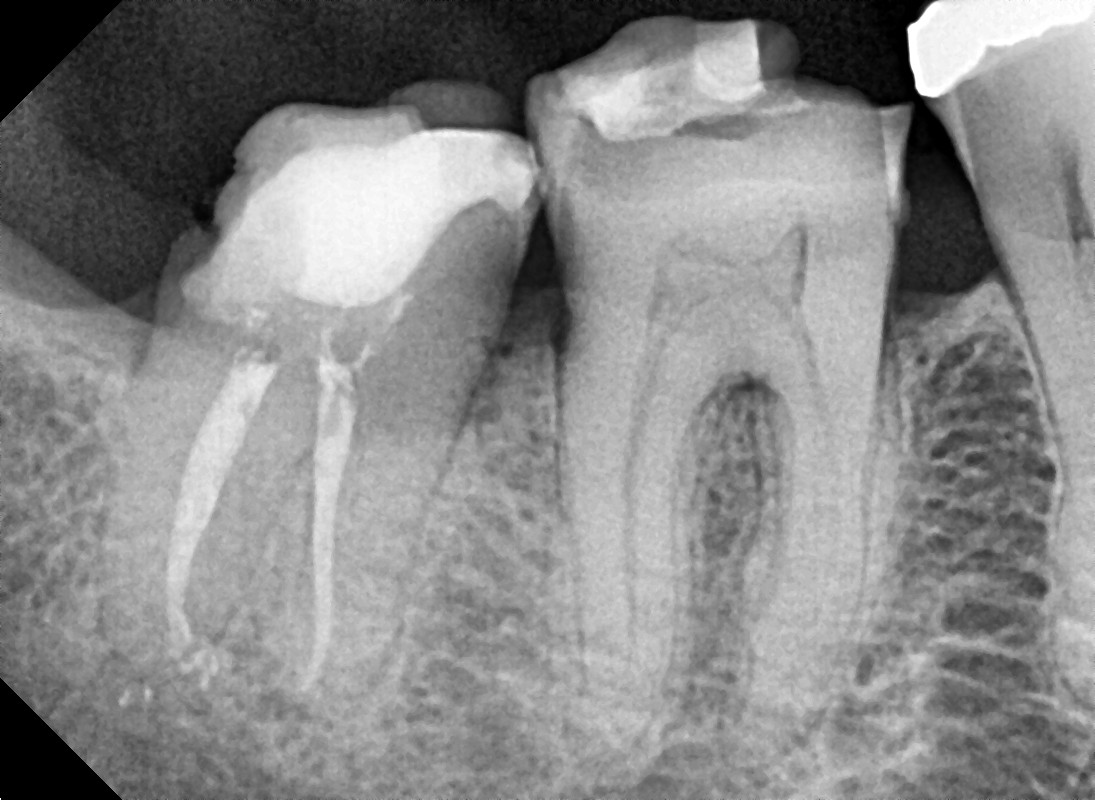

Rx Retroalveolar o Periapical

La radiografía retroalveolar es también llamada periapical y es muy útil para enfocarse en una zona determinada, porque permite evaluar en detalle el estado de dos o tres piezas dentarias